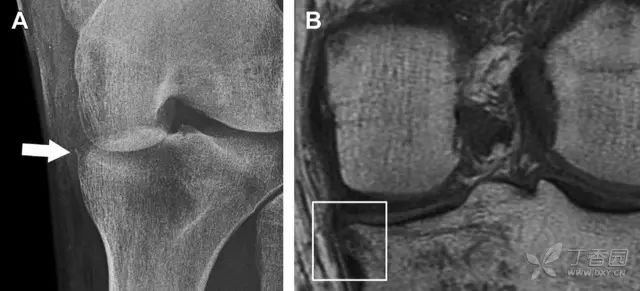

膝关节撕脱骨折和压缩骨折常伴发于韧带损伤,若想准确诊断,在了解这些骨折高发部位的同时,还需仔细认真地阅片,否则有些骨折就被漏诊了。

前交叉韧带撕脱骨折常发生在胫骨髁间嵴(图 1)。这种骨折在青少年中常见,但在成年人中也并不像大家想象的那么少见。

图 1 摩托车事故患者前交叉韧带撕脱性骨折

A 正位片示胫骨髁间嵴底部骨折(箭头),注意别把这个骨折碎片错认为关节内结构。B 侧位片示胫骨上方可见一细长型骨折碎片(椭圆)。C MRI 矢状位 T2 加权像示前交叉韧带附着于撕脱的骨折碎片上(箭头),注意周围存在骨髓水肿和积脂血征(空箭头)。